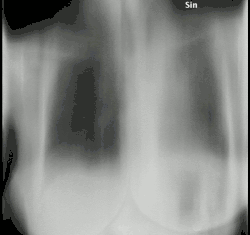

Tomosynthesis of a lung with chronic fibrosing pulmonary aspergillosis.